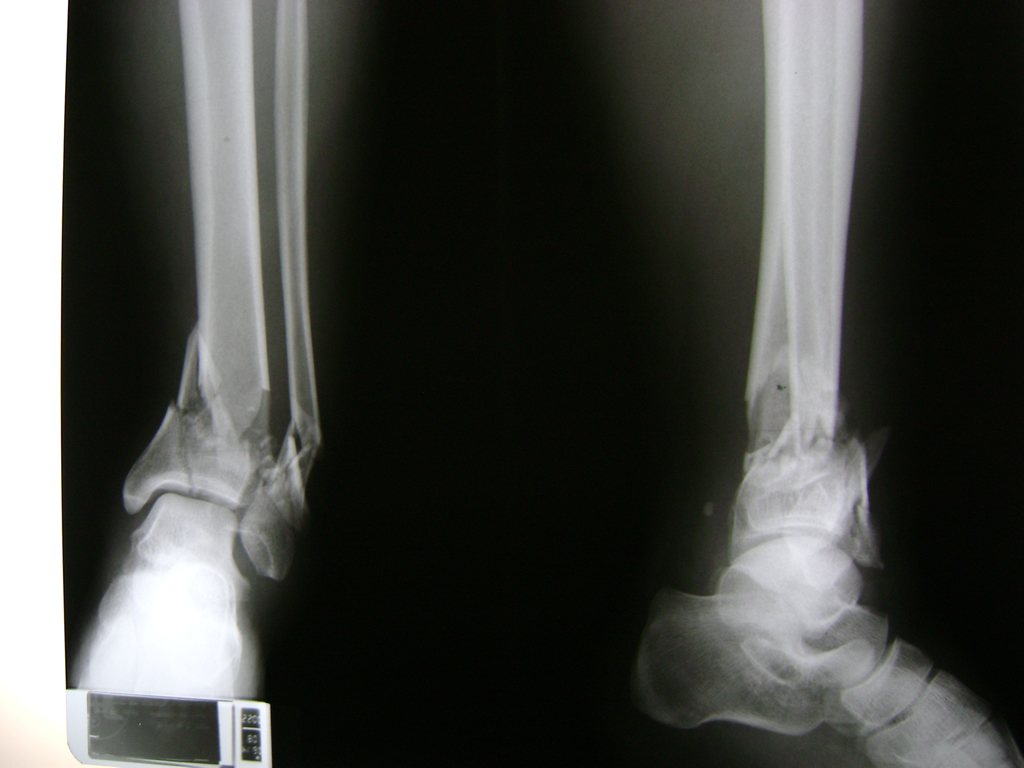

Una fractura de tobillo es la rotura de uno o más de los huesos del tobillo. Estas fracturas pueden ser:

- Producirse en uno o ambos lados del tobillo.

Algunas fracturas de tobillo pueden requerir cirugía si:

- Los extremos de los huesos están desalineados entre sí (desplazados).